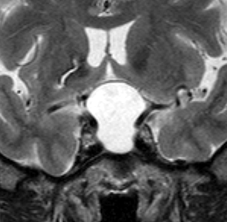

この患者さんは軽い下垂体機能低下症で発症しました。蝶形骨洞の中にのう胞が拡大していて,下垂体がぺったんこです。鞍上部には全く伸びていないので,視神経交叉は正常に見えます。この手術はとても簡単です,嚢胞をぷつんと破って液体を排出するだけにした方がいいでしょう。何故なら下垂体がうすく菲薄化funningしているので嚢胞壁を摘出しようとすると前葉機能を低下させるリスクが高いからです。